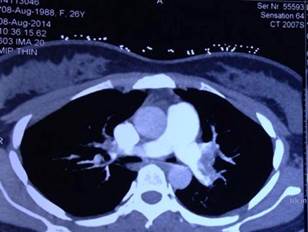

Tắc động mạch phổi cấp được nghi ngờ là nguyên nhân gây sốc, vì bệnh nhân có đau ngực, khó thở, nhịp tim nhanh, có thai 12 tuần và lâm sàng, điện tim có biểu hiện suy tim phải cấp. Chỉ định chụp cắt lớp vi tính (CLVT) động mạch phổi cấp cứu được xem xét. Theo Uỷ ban quốc tế về an toàn phóng xạ (The International Commission of Radiologic Protection), liều tia xạ khi chụp CLVT động mạch phổi phóng qua tử cung người mẹ không làm tăng nguy cơ tử vong hoặc dị tật thai nhi [1]. Bệnh nhân được chụp CLVT 64 dãy động mạch phổi, kết quả cho thấy huyết khối ở cả 2 động mạch phổi phải và trái với mức độ nặng (SI) CLVT là 50%.

Hình 3: Huyết khối ở động mạch phổi phải và trái (SI : 50%)Bệnh nhân được thở oxy, truyền dobutamin tĩnh mạch, dùng heparin bolus và truyền liên tục qua bơm tiêm điện và xem xét dùng thuốc tiêu sợi huyết cấp cứu.